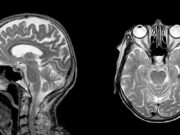

МРТ головного мозга: когда нужно делать и что показывает?

Магнитно-резонансная томография (МРТ) головного мозга – один из самых точных и безопасных методов диагностики. Она позволяет выявить различные патологии, оценить состояние тканей и сосудов,...